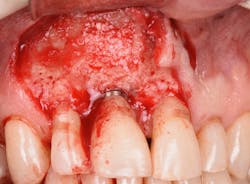

Figure 22: A regenerative approach was taken using a xenograft bone graft in combination with BB human recombinant platelet-derived growth factors.

Purchasing the Er:YAG laser can be beneficial to clinicians who desire a true hard- and soft-tissue laser. The amount of training is minimal, and the settings are similar for various applications. Since the Er:YAG laser has an affinity to water, it has been shown to have minimal thermal changes, and it promotes reduced postoperative discomfort. One study showed that when cutting bone for partially erupted third-molar extractions, not only less intra- and postoperative pain was noted, but also a reduction in facial swelling when compared to conventional bur drilling.13

Figure 23: A porcine 3-D volume stable collagen matrix was used not only as a barrier but also to enhance the thickness of the soft tissue. The matrix thickness measured 3 mm to achieve gingival horizontal volume.